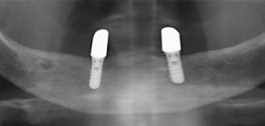

Implantation / Implantate

Vor nicht allzu langer Zeit bedeutete Zahnverlust häufig das Tragen von Teil- oder Vollprothesen. Die Praxis bietet mit dem Tätigkeitsschwerpunkt Implantologie den dauerhaft festsitzenden Zahnersatz für verloren gegangene Zähne.

Implantate sind künstliche, meist schraubenförmige Zahnwurzeln aus Titan oder Zirkondioxid und bieten das Fundament für einen stabilen Zahnersatz im Ober- beziehungsweise Unterkiefer. Reintitan und Zirkondioxid sind biokompatible Werkstoffe. Sie lösen in der Regel keine Allergien aus.

Zahnimplantate sind in der Regel zwischen 6 und 14 mm lang und haben einen Durchmesser von etwa 3 bis 6 mm. Dadurch, dass ein Implantat fest in den Kieferknochen einwächst, ist die Verankerung so fest wie bei einem gesunden eigenen Zahn.